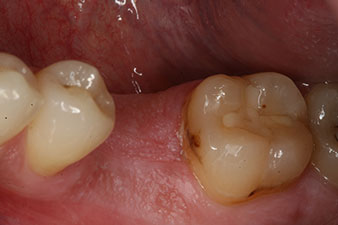

A 28-year-old patient with a history of heavy smoking had to have tooth 36 extracted as a result of recurring apical periodontitis.

Due to the generally intact neighbouring teeth the only way to fill the gap was an implant.

However, six weeks after the extraction incomplete ossification was found after preparation of the mucoperiosteal flap in the region of the former mesial alveolus.